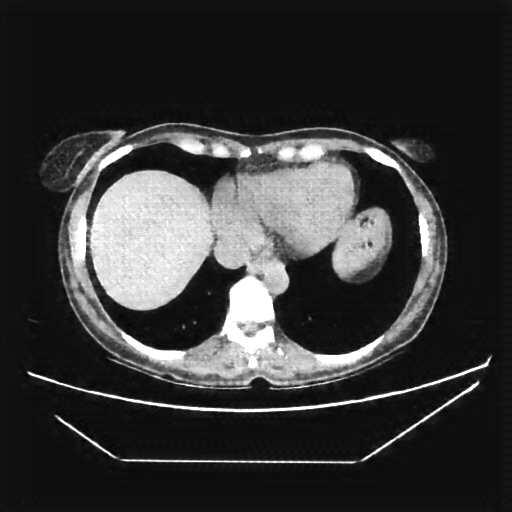

Reconstructed NATIVE CT scan (cycle consistency)

Full window (WL 1023.5, WW 4095 β†’ Low βˆ’1024, High +3071)

Actual HU range: [-832.9, 629.2]

Lung window (WL -600, WW 1500 β†’ Low βˆ’1350, High +150)